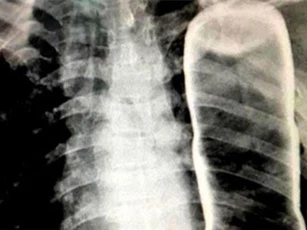

Vỏ chai thủy tinh chui vào ngực, ho ra tiếng kèn, con đỉa sống trong phổi... là những ca bệnh khiến bác sĩ cũng kinh ngạc.